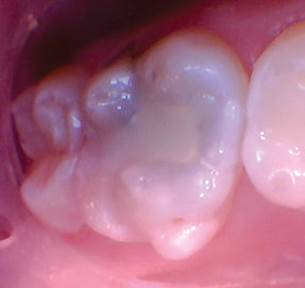

Figura 5. Esta pulpa exhibió una pulpa radicular sana como lo demuestra el sangrado fácilmente controlado. |

Figura 6. Se colocó una capa de 2-3 mm de Biodentine seguida de una capa de Ionoseal (Voco) para evitar el lavado de ATM al proceder con el proceso de restauración. |